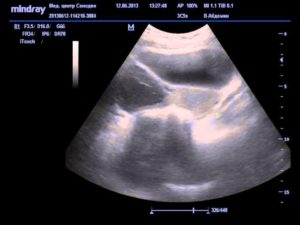

При помощи УЗИ гинеколог сможет увидеть не только угрозу, но и ее возможную причину (аномалия развития плода, предлежание и отслойку плаценты, признаки внутриутробного инфицирования, нарушение кровотока). При ультразвуковом исследовании всегда можно оценить состояние малыша и если потребуется, принять все возможные меры по сохранению беременности и спасению жизни плода.

Доктор произведет осмотр, во время которого оценит состояние матки и шейки матки, а также назначит УЗИ для оценки состояния плода.